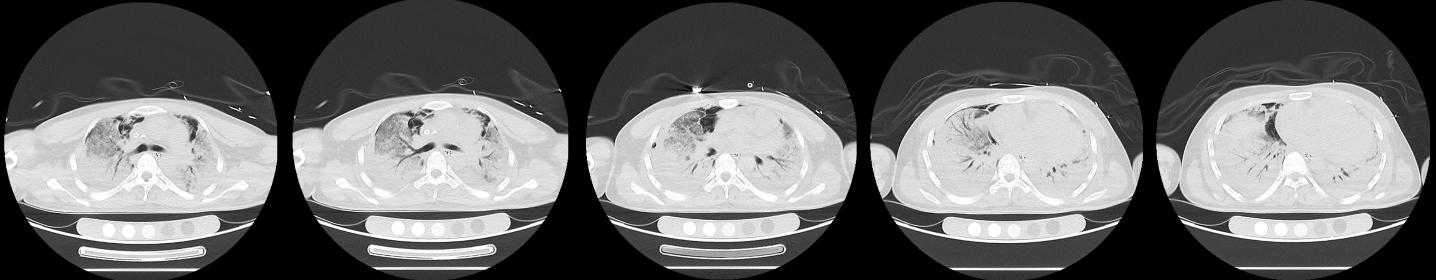

1 病例资料2024-11-15,某工地操作间有值班人员3人,分别为上铺(距地面1.8 m)A某,下铺(距地面0.4 m)B某、C某,事发当天为午休时间,设备出现故障,下午14时维修人员D某进入操作间维修,并将门窗打开,完成维修操作;事发后24 h内4名患者均出现不同程度的恶心、呕吐等消化道症状,起初考虑可能与食物中毒有关,前往当地医院就诊,完善血便常规、胸腹CT等相关检查未见明显异常,在医院给予吸氧补液静卧留观,留观期间4人先后出现不同程度的咽痛、咳嗽、胸闷、憋气等不适,吸氧不能缓解,再次行胸部CT检查示双肺弥漫性改变,间质改变可能,考虑为吸入有毒有害气体,后经采样检测操作间气体残留为全氟-4-甲基-2戊稀[Perfluoro(4-methylpent-2-ene),D1](D1纯度99.92%),导致急性呼吸窘迫综合症(acute respiratory distress syndrome, ARDS)。参照2002年职业性急性有机氟中毒诊断标准[1],A某诊断为急性中度有机氟气体中毒,B某、C某、D某诊断为急性重度有机氟气体中毒(PaO2/FiO2 < 100 mmHg,1 mmHg=0.098 kPa)。立即给予大剂量(120 mg)甲泼尼龙琥珀酸钠治疗,同时补充多种微量元素,加用甲钴胺、硫辛酸,钙剂解毒,后续加用特殊解毒剂乙酰胺治疗。治疗1周后,上铺的A某胸闷、憋气症状较前好转,影像未见明显进展,但患者仍遗留有间断气短症状;其余人员病情持续恶化,出现呼吸衰竭,转入重症医学科,给予气管插管接呼吸机辅助通气,维修人员D某上呼吸机后能基本维持,但不能脱机,继续观察患者病情变化;而下铺患者B某、C某症状不断加重,即使给予呼吸机治疗低氧状态仍未见明显改善,于2024-11-29转入本院进一步治疗。B某、C某入本院时查体:双肺叩诊呈清音,双肺呼吸音粗,可闻及干湿性啰音,具体指标见表 1,图 1、2为肺部影像进展情况。入院给予镇静镇痛、机械通气及抗感染、抗炎、抑酸等治疗,呼吸困难仍持续加重,存在难以纠正的低氧血症及高碳酸血症,表现为ARDS,有体外膜肺氧合(extracorporeal membrane oxygenation, ECMO)治疗指征,参考国内外相关救治经验[2-6],给予患者静脉-静脉ECMO(veno-venous extracorporeal membrane oxygenation, V-V ECMO)治疗,具体参数见表 2。

| 图 1 B某发病第1、3、10天胸部CT |

| 图 2 C某发病第1、3、10天胸部CT |